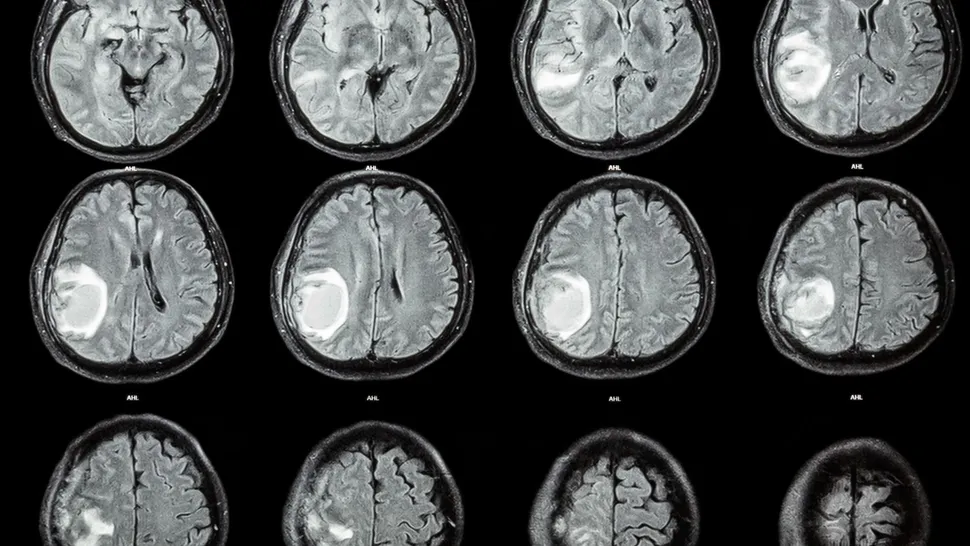

Doctors found a malformed fetus in an infant's brain. (These brain scans are stock images and not from the case report described below.) (Image credit: stockdevil via Getty Images)